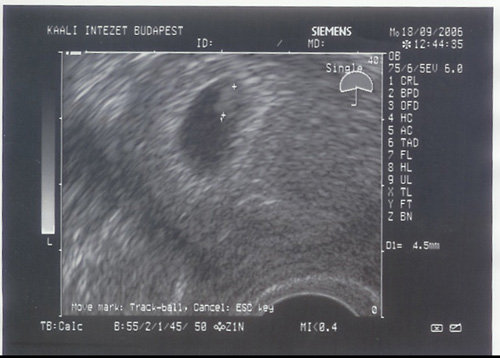

Gyors bejelentkezés az UH képpel:

Apa is bent volt velem, Ő is látta a pulzáló szívecskéjét. Kép

Még csak óvatosan örülünk... Kezem-lábam remegett végig, hogy mi lesz (bár még most is egy kicsit...).

Következő UH 2 hét múlva, hétfőn.

Gartulálok!nagyon aranyos!Jól látom, hogy 4.5 mm?